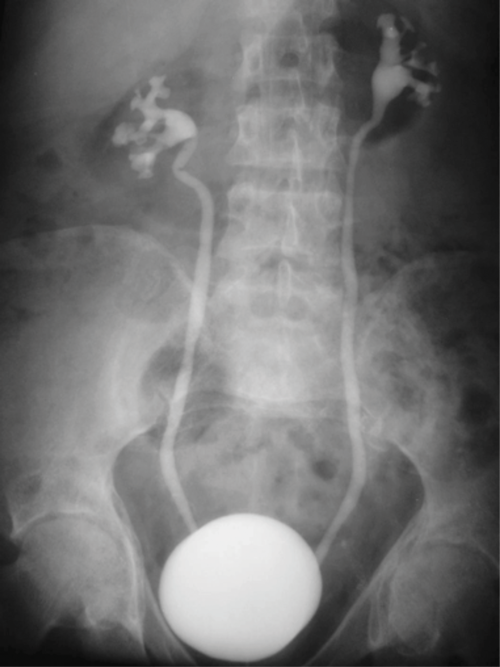

Case 3

A 42-year-old female patient.

1. What radiological examination has been undertaken?

2. Describe the findings on the image.

3. What is your diagnosis?

- A cystogram has been performed. Although the image looks like an intravenous urogram (IVU), the bladder is too densely opacified with contrast for this to be part of an IVU series. The bladder has been distended with contrast during the cystogram.

- Dense opacification of the urinary bladder is seen, which has a smooth outline and appears normal. Contrast is seen to reflux into both ureters and collecting systems which should not be seen as part of a routine cystogram.

- The patient has marked reflux (grade 4). Reflux is graded from 1 to 5, as below:

- Grade 1 - reflux limited to the ureter

- Grade 2 - reflux up to the renal pelvis

- Grade 3 - mild dilatation of the ureter and pelvicalyceal system

- Grade 4 - tortuous ureter with moderate dilatation

- Grade 5 - tortuous ureter with severe dilatation of ureter and pelvicalyceal system. Loss of fornices and papillary impressions.

Sometimes, reflux is not seen during a routine cystogram, but if there is clinical suspicion, further images should be obtained during micturition to assess for mild reflux.